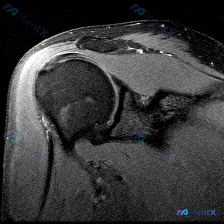

整理了一个肩关节MRI-T2序列冠状位的病例讨论材料,医生提问关注盂唇病变,但影像最突出的是冈上肌腱全层撕裂。这份病例的核心疑问点和影像发现存在一定不匹配,大家第一眼怎么看?

整理了一份有意思的肩关节MRI读片病例,问题一开始聚焦在「软组织积液」上,但梳理下来发现这个病例很容易踩坑,分享一下我的思路。 一、影像基本信息 这是一份肩关节冠状位T2序列MRI,我们按结构逐层看一下观察到的征象: 1. 冈上肌腱:肱骨大结节止点处可见条带状局灶异常高信号,贯穿肌腱全层,从关节面延...

整理了一份肩关节MRI的病例资料,临床申请的检查目的是排查盂唇病变,不过仔细阅片后发现核心异常好像不在盂唇那边? 先放已明确的影像基础信息: - 序列修正:初始标注为T1序列,实际影像符合质子密度压脂(PD FS)或T2压脂序列特征,对积液、肌腱损伤敏感 - 核心可见表现:肱骨大结节处肌腱信号异常、...

看到一个肩关节MRI影像分析的病例材料,影像为冠状位T2加权图像,主要发现如下: 1. 冈上肌腱远端附着处全层撕裂,T2序列显示高信号液体填充 2. 肩峰下-三角肌下滑囊内有明显积液 3. 盂肱关节腔内有显著液体潴留 用户的核心问题是关于「盂唇病变」的可能性。这个病例有几个点值得讨论: - 冈上肌腱...